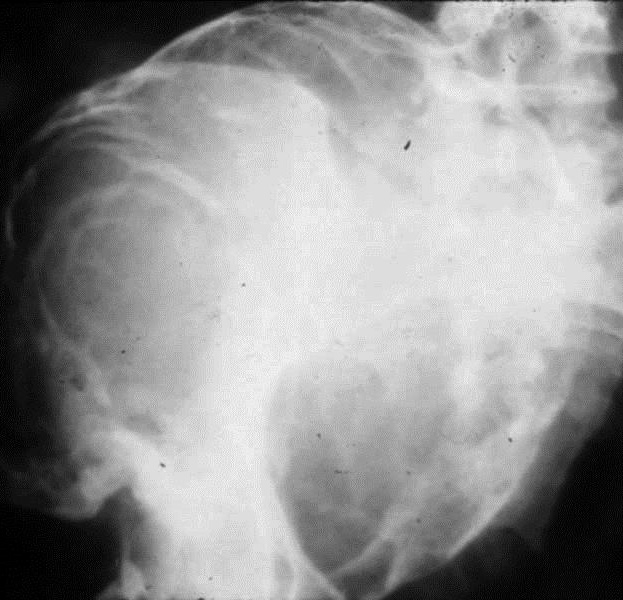

Hemophilic patients at times present a cystic lesion filled with blood as a rare complication. Repeated intraosseous bleeding produces a well defined uni or multilocular lytic expanding lesion. These are located either in metaphysis or epiphysis (Figure 15).

Figure 15: Pseudotumor hemophili with large lucent multilayered lesion in the iliac bone.